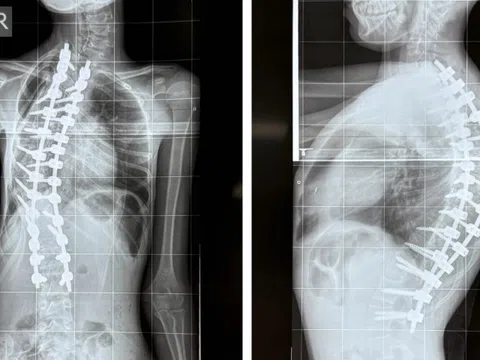

Bé gái mắc bệnh hiếm, bác sĩ BV Nhi đồng 1 lần đầu gặp

Ê-kíp Bệnh viện Nhi Đồng 1 phối hợp bệnh viện Chấn thương Chỉnh hình TP.HCM cứu hai bé gái có vẹo cột sống trên...